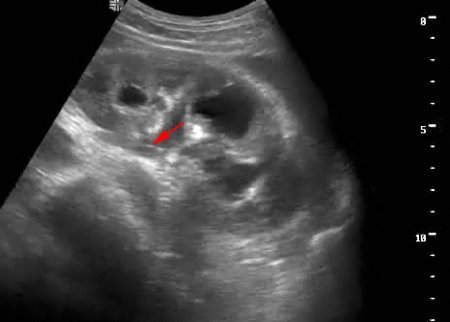

Пациент с подтвержденным туберкулезом почки

Вот как выглядит почка при первом осмотре и в феврале

Видим длительно существующий гидронефроз вследствие процесса в области лоханочно-мочеточникового сегмента (видео 1), с утолщением стенок ЧЛС и истончением паренхимы почки - наиболее частая причина у взрослых - туберкулез.